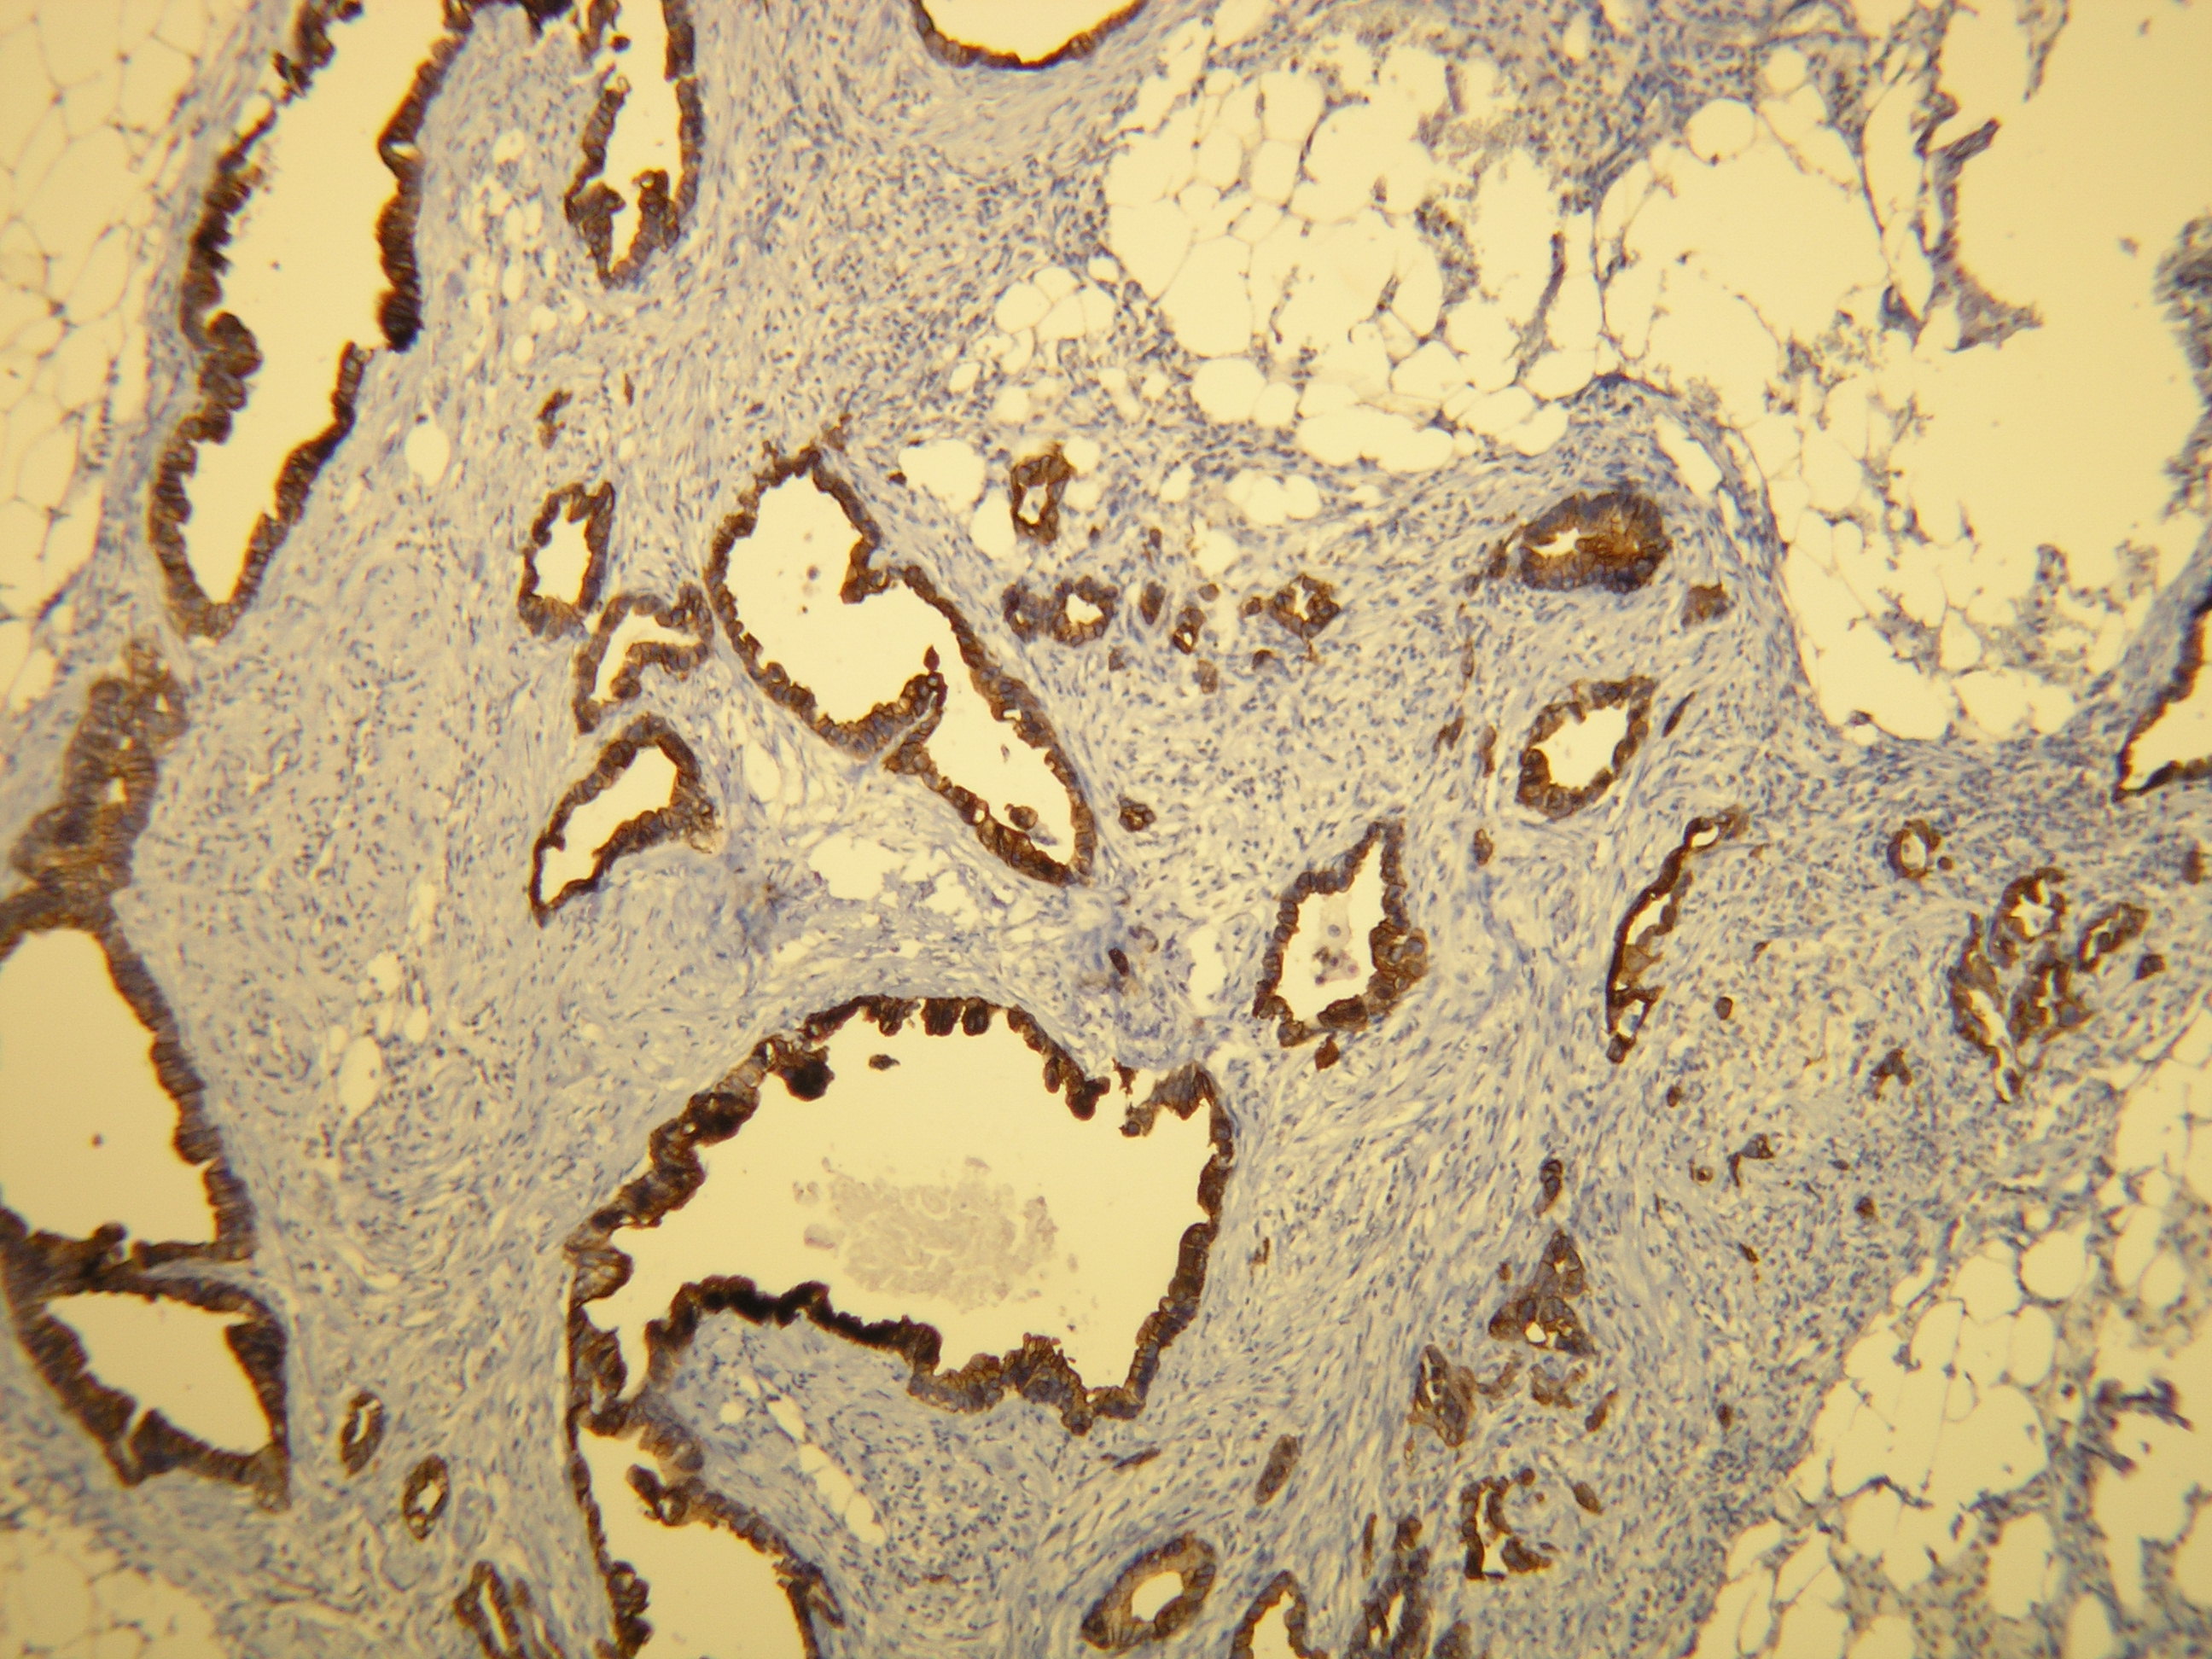

Anti-Cytokeratin 7

Peptid derivovaný z N-koncovej sekvencie ľudského cytokeratin 7. Protilátka rozpoznáva epitop umiestnený medzi Ala22 - Ser38.

Aplikácia

IHC-P, riedenie 1:100

db051 db051b db051c